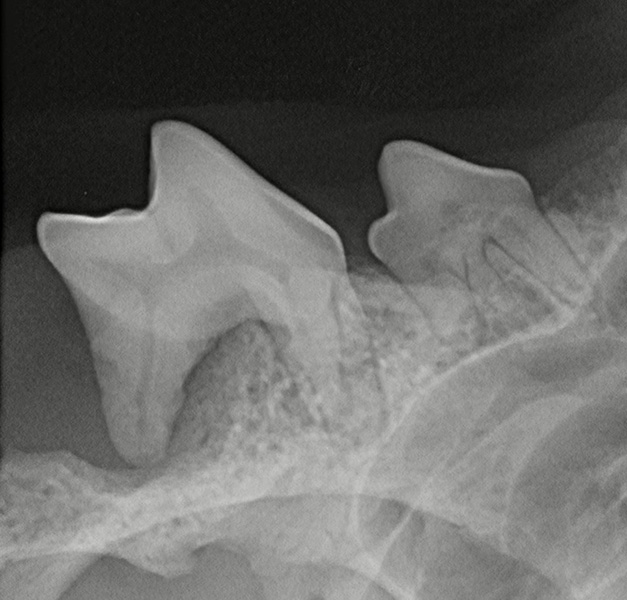

Ebenfalls steht uns ein modernes Dentalröntgengerät zur Verfügung.

Für aufwendigere Zahnsanierungen mit Extraktionen von Zähnen, die nicht erhalten werden können, oder von persistierenden Milchzähnen (meist Canini) sowie Paradontitisbehandlungen werden Vollnarkosen wahlweise als Inhalations-oder Injektionsnarkose eingesetzt – auch abhängig vom

Gesundheitszustand der Patienten. Oft sind Röntgenaufnahmen und auch ein präoperatives Labor zu empfehlen. Dieses wird vor der Zahnbehandlung mit Ihnen gemeinsam besprochen. Wir beraten Sie auch gerne zur Zahnpflege der Zähne Ihrer Vierbeiner.